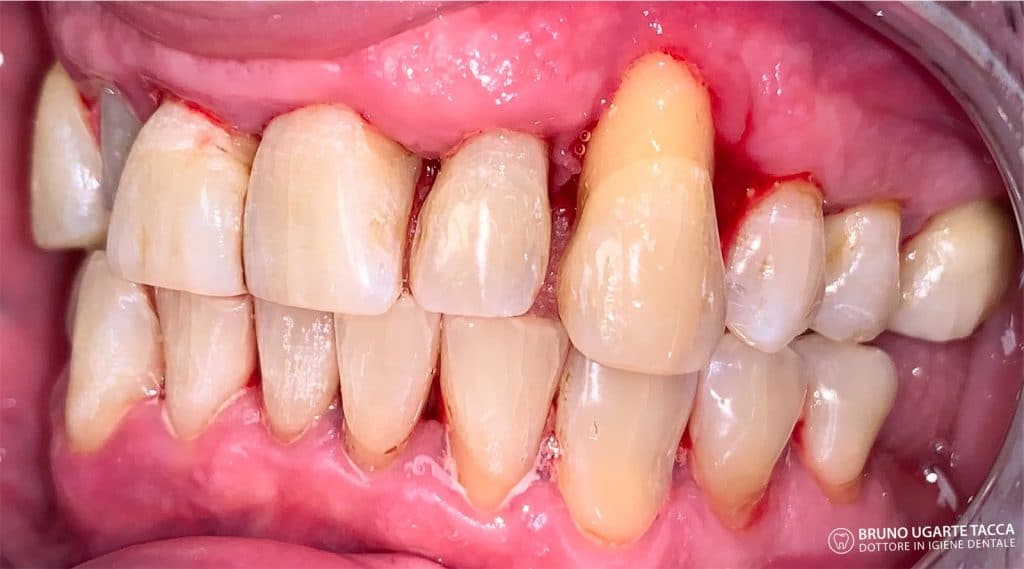

Performing the complete instrumentation

supragingival and subgingival with ultrasonic and / or manual instruments in one

single session or in two sessions at most performed over 2 days